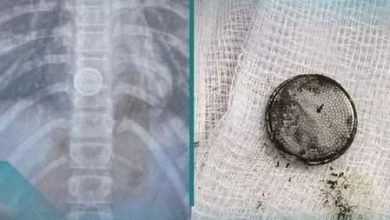

انقاذ طفلة بلعت جسما غريبا في الديوانية

انقذ فريق طبي متخصص في مستشفى الديوانية التعليمي حياة طفلة تبلغ من العمر (12) عاماً،…